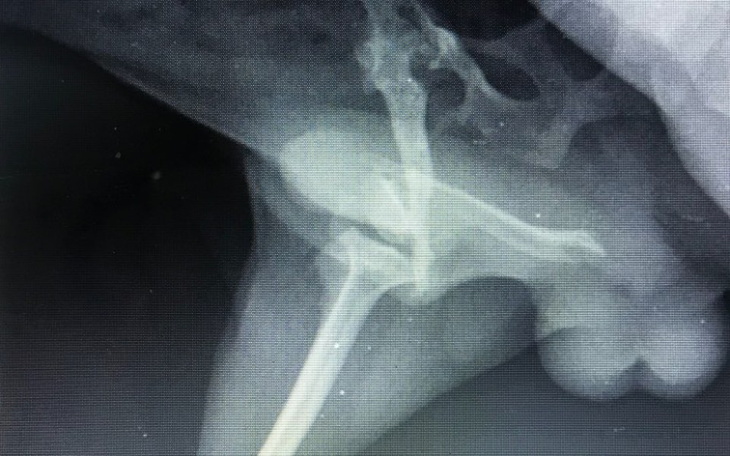

Benek trafił pod moją opiekę 23 lipca bieżącego roku. Maluch przyplątał się do znajomej na spacerze. Wsiadłam w auto i pojechałam ponad 50 km w jedna stronę, żeby go zabezpieczyć. Pomyślałam sobie, że może tylko się zgubił, dodam ogłoszenia i szybko właściciel się znajdzie. Szybko zderzyłam się z rzeczywistością. Zanim dotarłam na miejsce było już ciemno, wsadziłam psa do transporteka i wróciliśmy do domu. Dopiero po wypakowaniu go z samochodu i wypuszczeniu w pokoju wiele się wyjaśniło. Noga jest krótsza, cieńsza i w ogóle nic nie jest na miejscu. Oczywiście pchły to codzienność każdego błąkającego się psa i tak też było i tutaj. Benek jest już po pierwszej konsultacji. Miał zrobione zdjęcie rentgenowskie. Rokowania nie są najlepsze. To bardzo stary uraz. Ktoś wtedy zostawił go samego sobie i wszystko pozrastało się tak jak chciało. Nie chce nawet myśleć jak musiał cierpieć. Amputacja to dla nas ostateczność dlatego nadal szukamy innego rozwiązania.

100 zł pierwsza konsultacja Benka w Kielcach.